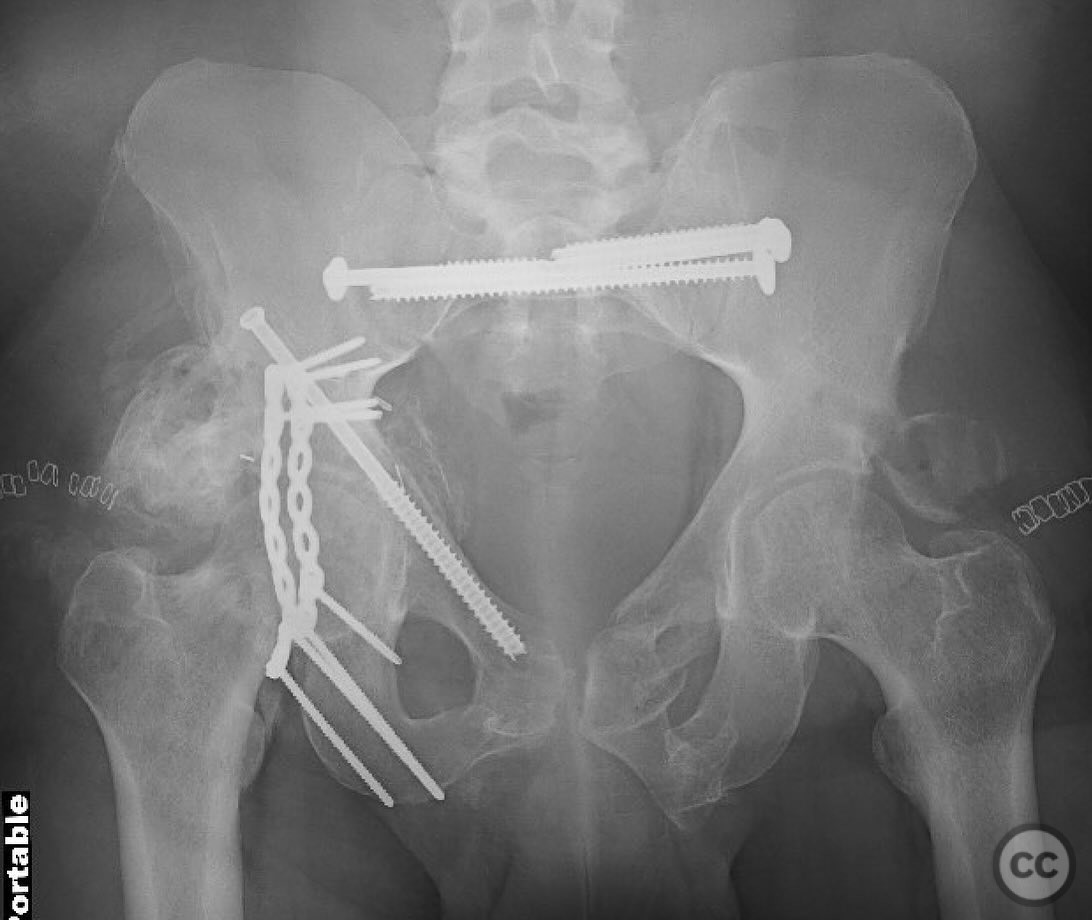

Combined Pelvic Ring and Transverse Acetabulum Fracture with Bladder Injury

Clinical and radiological findings:  The patient presented with a highly unstable pelvic ring injury and a transverse acetabulum fracture, accompanied by a bladder injury. The bladder injury was addressed emergently with a low vertical midline Pfannenstiel incision for repair, followed by the placement of a low right-sided suprapubic catheter. Radiological imaging confirmed the transverse acetabular fracture and disruption of the left sacroiliac joint, along with a displaced sacral fracture.

Orthopaedic implants used:   Lag screws for sacroiliac joint and sacral fracture fixation, external fixator for posterior ring stabilization, potential plate and screw constructs for acetabular ORIF through Kocher-Langenbeck and modified Stoppa approaches.